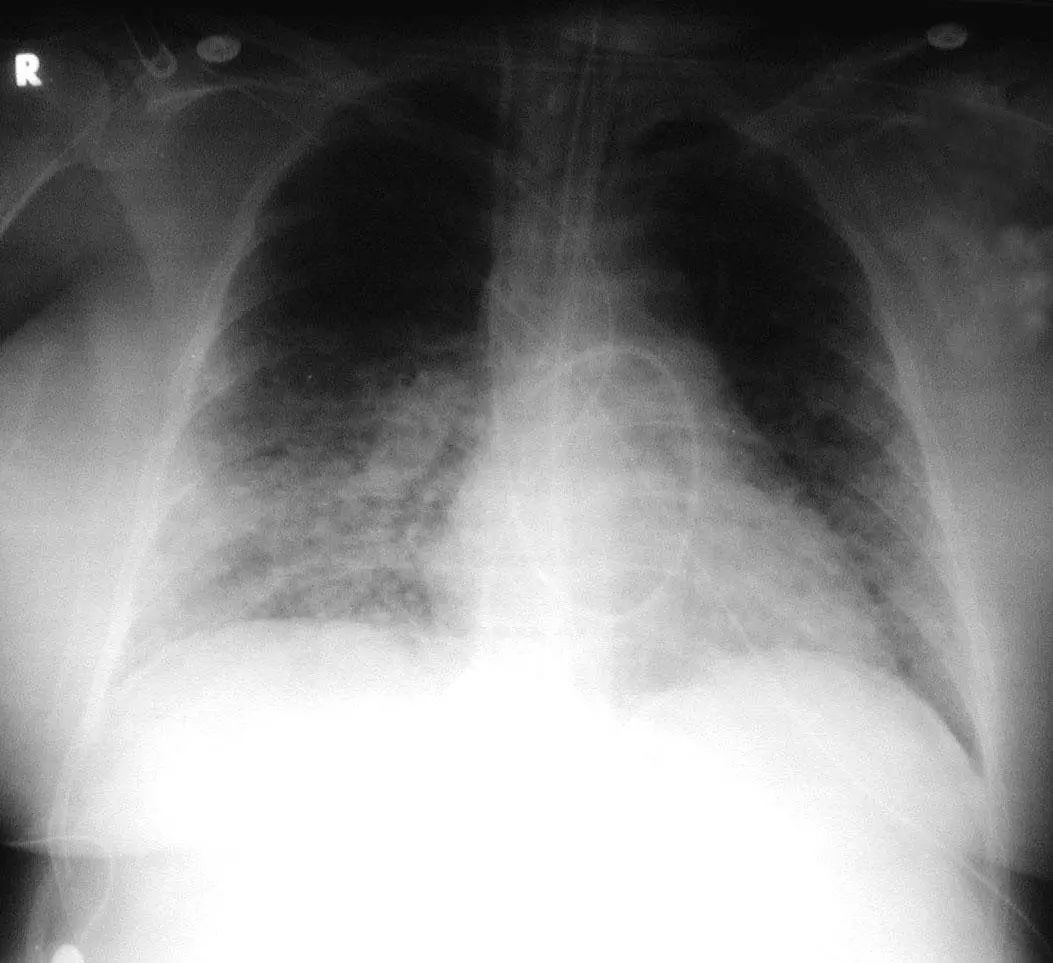

图1.4 53岁的严重军团菌肺炎患者。胸片显示双肺下叶致密实变。